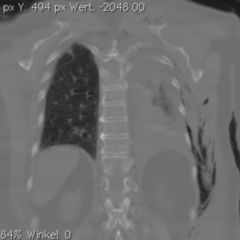

Unter einem Hautemphysem (auch Unterhautemphysem oder subkutanes Emphysem) versteht man eine Ansammlung von Gas in der Unterhaut nach spontaner oder verletzungsbedingter Eröffnung lufthaltiger Organe, z. B. der Lunge.

Ein Hautemphysem kann durch Verletzungen luftgefüllter Organe (Lunge, Luftröhre, Speiseröhre etc.) oder durch gasbildende Bakterien verursacht werden. Das Emphysem kann beispielsweise in Folge eines randständigen Lungenrisses mit Anschluss an das Mediastinum nach einem Tauchunfall auftreten. Sie kann auch als Komplikation nach ausgeführter Luftfüllung von Körperhöhlen aufgrund medizinischer Diagnostik entstehen oder aber nach Infektionen mit gasbildenden Erregern unter der Haut. Großflächige Hautemphyseme können z. B. durch einen Spannungspneumothorax, einen Thoraxriss oder Schädelbasisbruch mit Eröffnung der Nasennebenhöhlen entstehen.